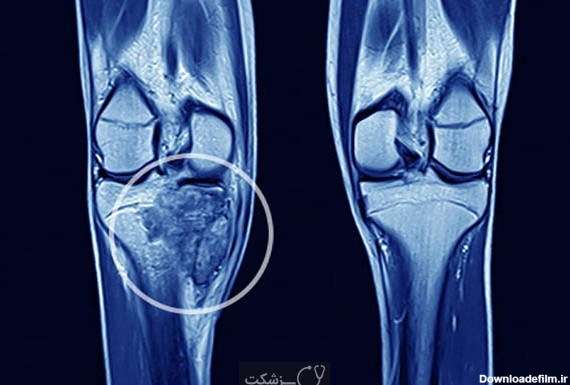

عکس تومور ساق پا

تومور ساق پا اگر ساق پای شخصی آسیب ببیند احتمالا روی پایش برجسته شده و دچار التهاب موقت می شود. با وجود این، هیچ دلیل آشکاری برای علت به وجود آمدن این گونه برجستگی ها و توده روی ساق پا وجود ندارد؛ اما امکان دارد که بعضی از این برآمدگی ها گویای شرایط و بیماری […]